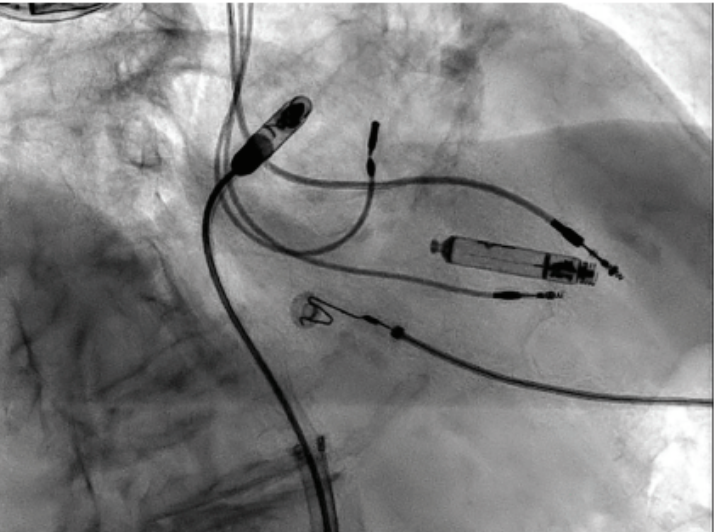

She was referred for consideration of extraction and reimplantation vs leadless pacemaker. Twelve-lead electrocardiogram (ECG) demonstrated a

ventricular paced rhythm at 61 beats per minute (bpm) (Figure 1). Device interrogation revealed increased RV lead noise, noise reversion, and inhibition resulting in inappropriate failure to output. Atrial parameters were unremarkable. Ventricular parameters were significant for an elevated capture threshold of 1.75 V at 0.4 ms, and labile impedances were consistent with impending fracture. We believe the recurrent fractures were due to the right-sided nature of the implant, tortuous vasculature, and the patient’s active lifestyle.